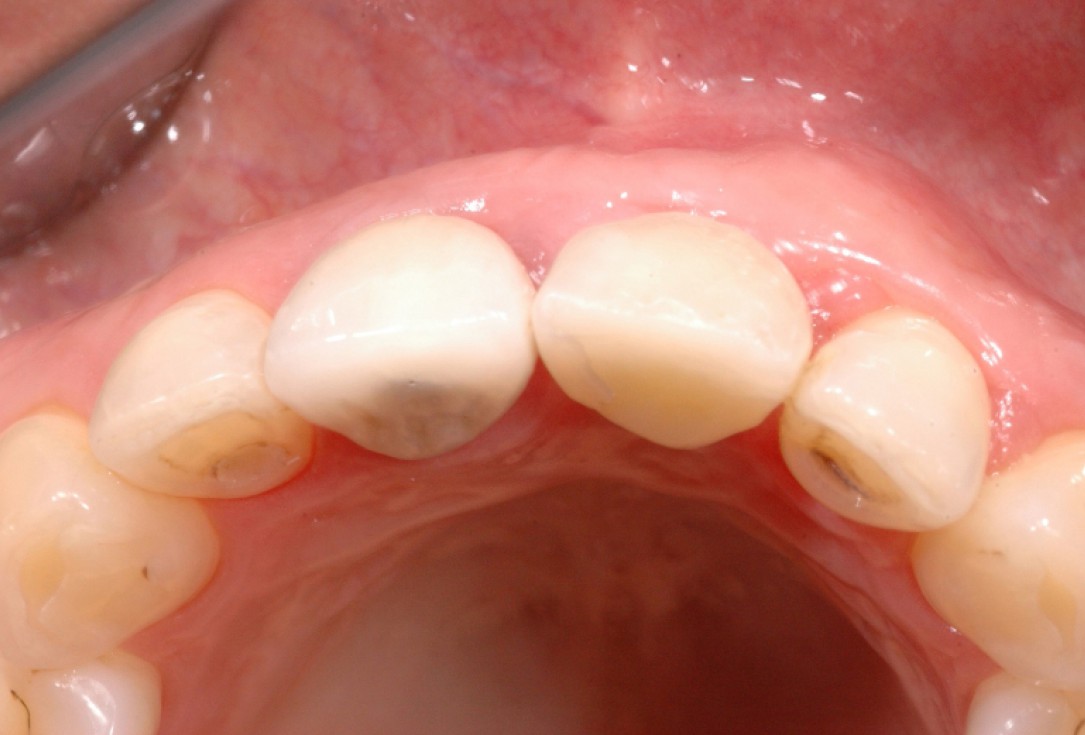

4/18 - Clinical situation, occlusal viewGBR together with soft tissue augmentation with mucoderm® and maxresorb® - Dr. S. Scherg